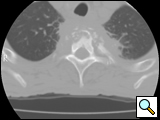

After completion of the spinal procedure, reorientation of the thoracic surgeon by the spinal surgeon is performed, including visualization of the implanted hardware and an explanation of the procedure that was performed (Figures 9a-c). Hemostasis is secured, the chest irrigated, and the posterior mediastinum is inspected for lymph leak (the presence of a CSF leak must be ruled out by the spine surgeon prior to this point in the operation). The diaphragm, if mobilized, is reattached to the fascia of the posterior chest wall with interrupted horizontal 0 prolene sutures or is anchored around the rib. A 28 Fr chest tube is placed in the posterior mediastinum and the chest is closed in a standard fashion. Postoperative spine imaging is necessary to demonstrate adequate position of the hardware and correction of the vertebral defect (Figures 10a-e, Video).

| Figure 10a-e: CT of spine after fixation | Figure 10b | Figure 10c |